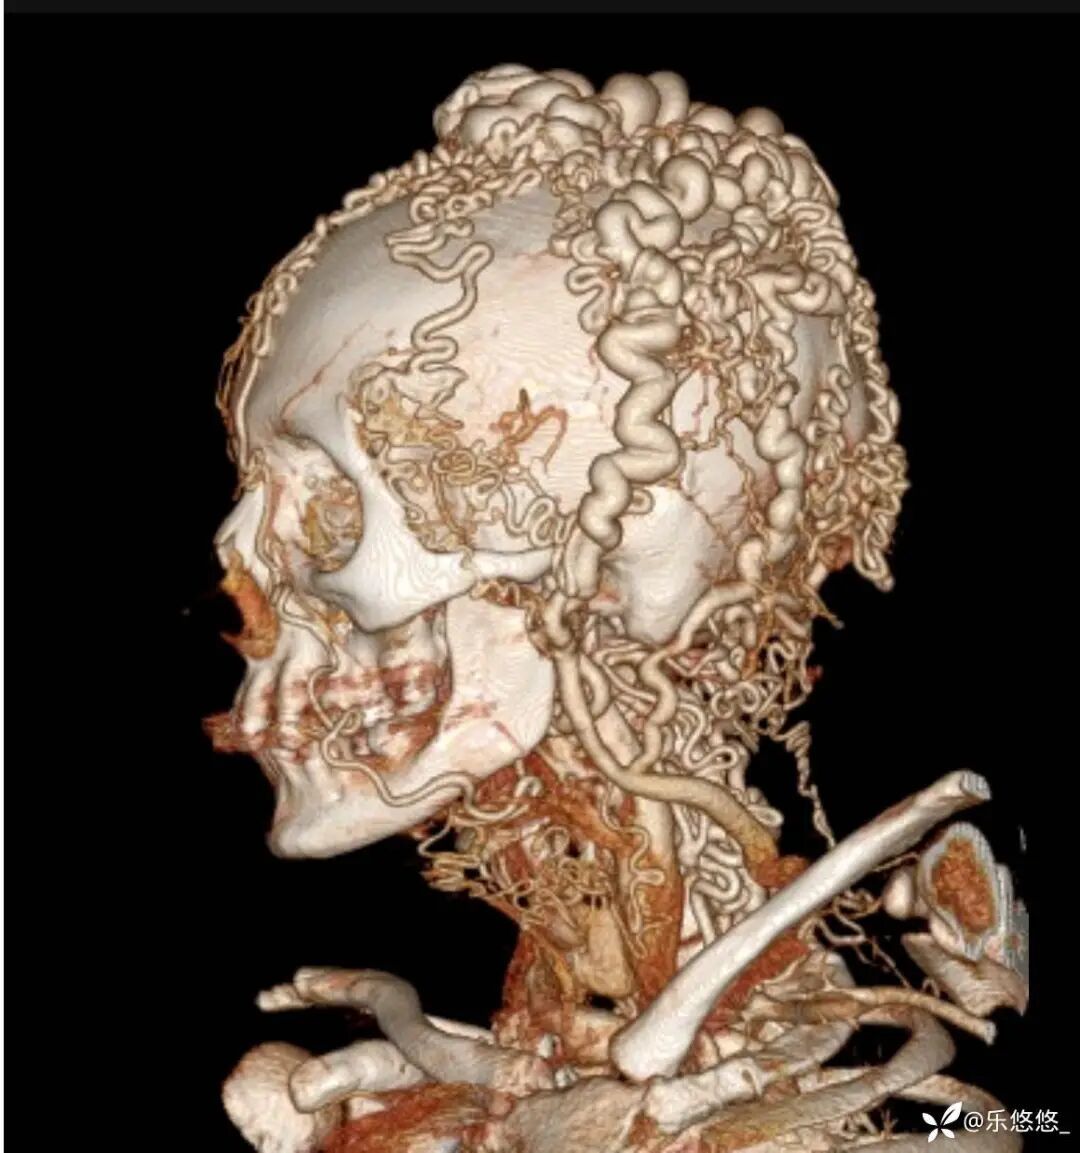

三维重建 CT 血管造影显示:头皮软组织层有多条扩张、迂曲的静脉血管。